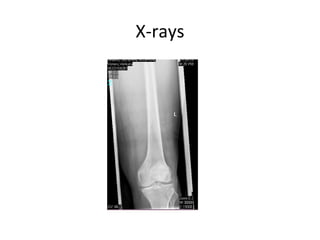

X-rays

Subtrochenteric femur fracture

• Subtrochanteric area typically defined as area

from lesser trochanter to 5cm distal.

• fractures with an associated intertrochanteric

component may be called intertrochanteric

fracture with subtrochanteric extension or

peritrochanteric fracture